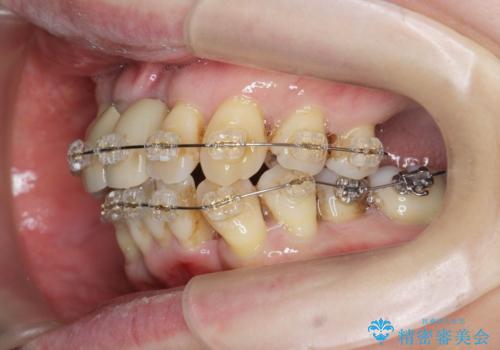

- 矯正装置

- ワイヤー矯正

- 治療期間

- 3年

このままの歯並びでは仮にインプラントを埋入したとしても歯ブラシがしづらく、また歯周病の問題が再発しやすい、と判断し矯正治療を行ったのちに歯周病治療、インプラント治療を行っていく治療計画としました。